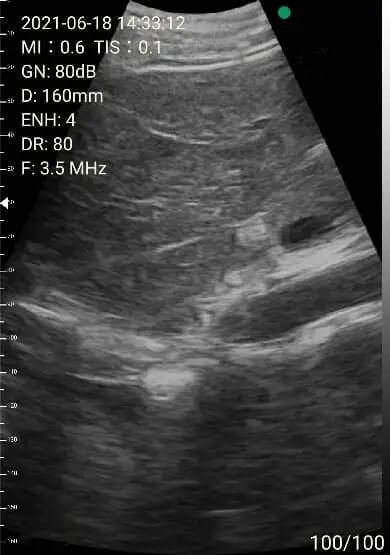

2. Abdomen review

Left lobe of liver

Portal area

Right lobe of liver

Images of thyoid scan on a 35-year-old healthy man.